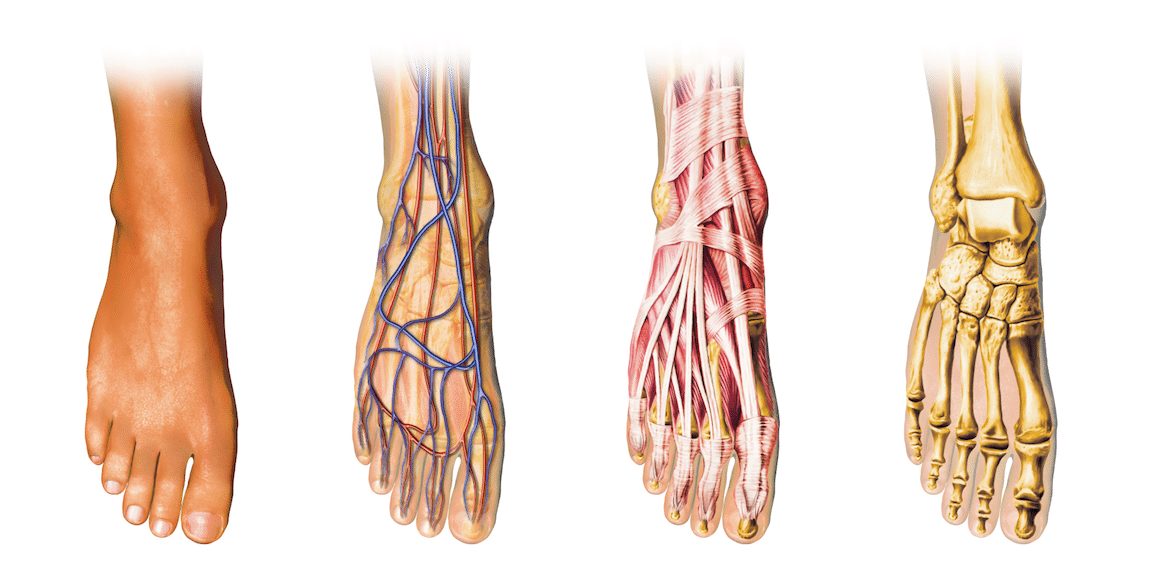

Votre pied a sa propre morphologie (taille, volume, forme).

On parle communément de pied normal, pied creux ou pied plat, mais il existe une infinité de combinaisons entre taille, volume et forme. Il laisse une empreinte absolument unique au monde.